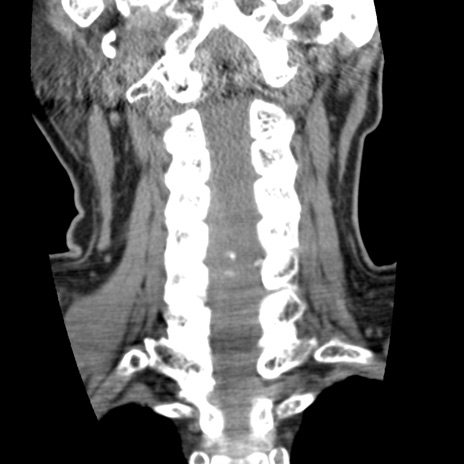

症例50 頚椎CT(冠状断像)

頚椎CT